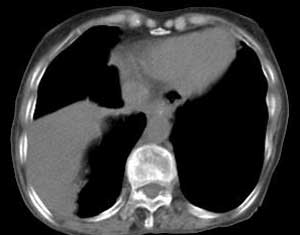

右肺门肿块影,中间段支气管以及右下叶支气管被浸润、堵塞,伴纵隔内淋巴结转移以及阻塞性肺炎。右肺中心型肺癌,堵的还很实在啊

右肺下叶中心性肺癌,阻塞性肺炎。

右肺下叶中心性肺癌,阻塞性肺炎

右肺下叶中心性肺癌,阻塞性肺炎及段性肺不胀。纵隔淋巴结转移。右上肺陈旧性肺结核。

右肺下叶中心性肺癌,阻塞性不张

右肺下叶中心性肺癌,阻塞性肺炎及段性肺不张。纵隔淋巴结转移.

右肺下叶中心性肺癌,阻塞性肺炎及肺不张,纵隔淋巴结转移.